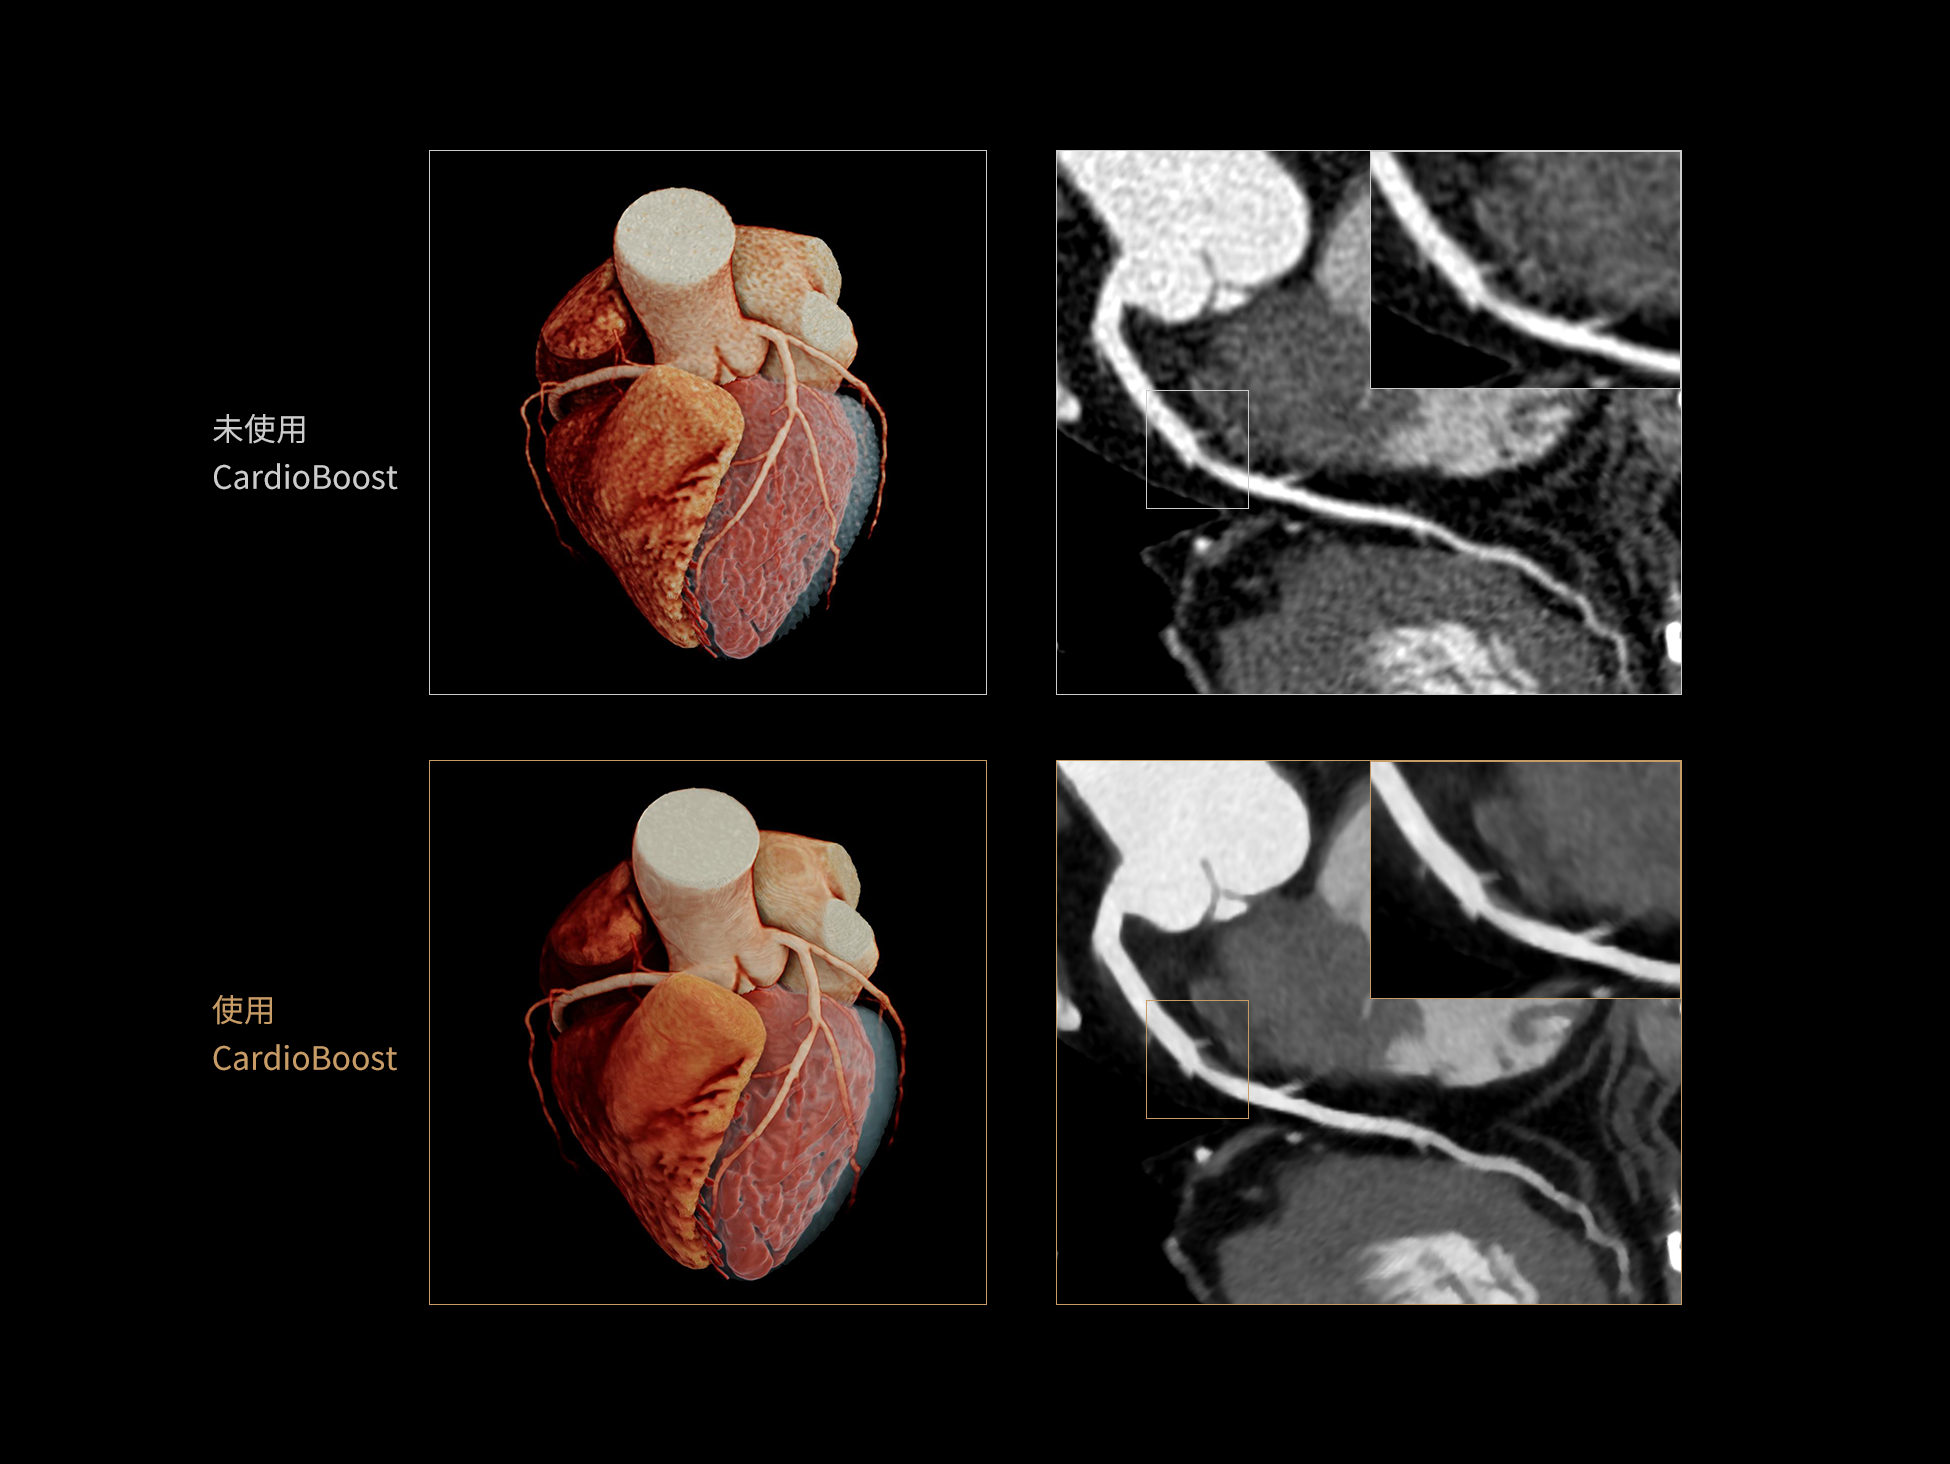

低对比度分辨率提升

相同辐射剂量下